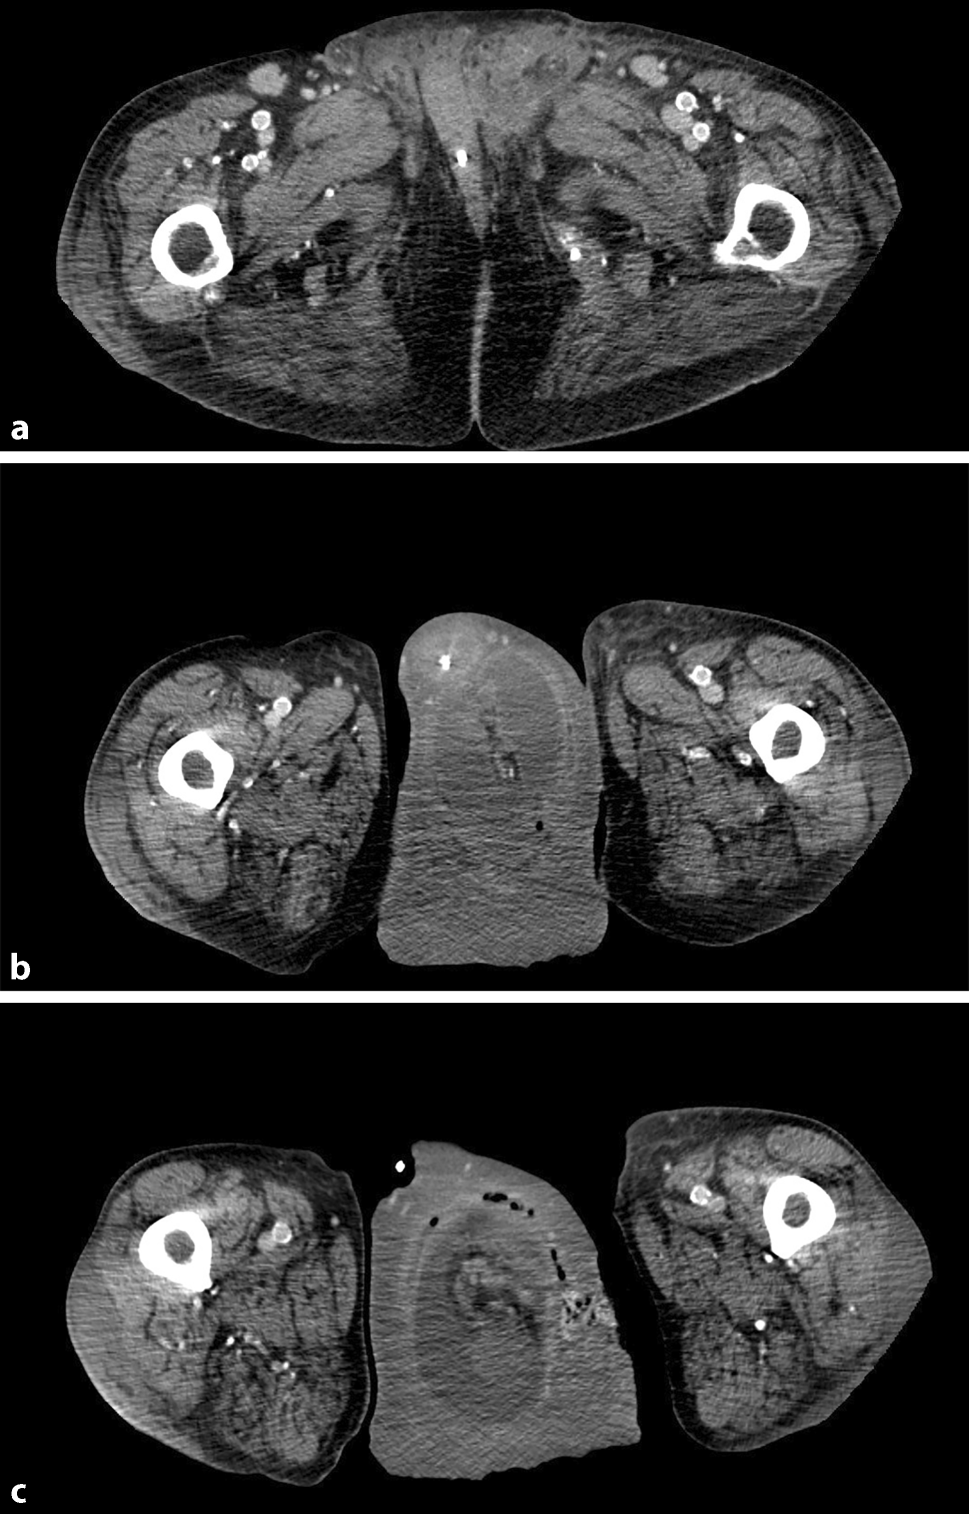

Patient information

The 73-year-old male patient was 173 cm tall and weighed 83 kg (BMI: 27.7 kg/m2). On initial presentation, he was suffering from a right-sided hernia (pL3) and a left-sided, partially reducible hernia with loss of domain (pL3) without previous abdominal surgery (Fig. 1). Coexisting medical conditions included peripheral vascular disease of the legs, grade II mitral valve failure, grade II tricuspid valve failure, atrial fibrillation, arterial hypertension, and ongoing nicotine abuse. The latter was terminated 4 weeks before the first hernia repair. This was conducted by means of a Lichtenstein operation. Botulinum toxin A (BOTOX® 100 Allergan international units, Allergan Pharmaceuticals, Westport, Ireland) was then administered to the three muscles of the abdominal wall in five positions on either side under ultrasound guidance and after dilution in 30 ml of normal saline. A CT scan was performed, which showed a loss of domain of 43% (volumes: hernia sac: 3670 ml, hydrocele 623 ml, abdominal cavity 7051 ml). Five weeks later, surgery was performed on the giant scrotal hernia on the left side. Lichtenstein’s technique of repair was chosen for the patient over potentially applicable laparoscopic procedures in view of the very large hernia and the patient’s general frailty. After a minimal additional lateral incision of the deep inguinal ring, in order to facilitate reduction of the hernia sac’s content, followed by nonabsorbable suture reconstruction of the deep inguinal ring, the implant size was chosen with regard to the patients limited anatomical space. The spermatic cord and testicle remained intact and could be preserved.

Subsequently, relaxation by means of botulinum toxin A (BOTOX® 100 Allergan international units) was planned to relax the abdominal wall sufficiently for the scheduled treatment of the much larger left-sided scrotal hernia. For preoperative optimization, especially for the creation of increased abdominal volume, a chemical myofascial relaxation with ultrasound-guided intramuscular infiltration of the three layers of the lateral abdominal wall muscles on both sides was performed with a total of 500 IU botulinum toxin A (BOTOX® 100 Allergan international units) divided into ten equal portions, which was the surgical unit‘s standard at that point in time and has since been reduced to 300 i.u. for this and similar indications. After uneventful observation overnight, the patient was discharged home. Five weeks later he was readmitted and underwent surgery for the left-sided giant scrotal hernia: after intraoperative placement of an indwelling urinary catheter, designed for monitoring the intra-abdominal pressure, the concomitant hydrocele in the left scrotum was drained and repaired with Winkelmann’s technique [8]. After herniotomy, the contents of the actual hernia sac could easily be reduced into the abdominal cavity. The detected hernia (EHS: pL3) was repaired with a self-gripping polypropylene implant (Covidien® Progrip 12 × 8 cm, PP1208D, Covidien/Medtronic, Devoux, France) with one additional, nonabsorbable suture fixation to the conjoint tendon in Lichtenstein’s technique [9]. Excessive scrotal skin was resected. Suction drains were placed in the scrotum and implant area for 3 days. The patient was transferred to the intermediate care unit for postoperative observation. Despite unsuspicious monitoring of his intra-abdominal pressure, the patient developed prerenal kidney failure, eventually attributed to overly restrictive intraoperative fluid management (Clavien–Dindo 3A) [10]. The condition was successfully managed conservatively by administration of crystalloid fluids.